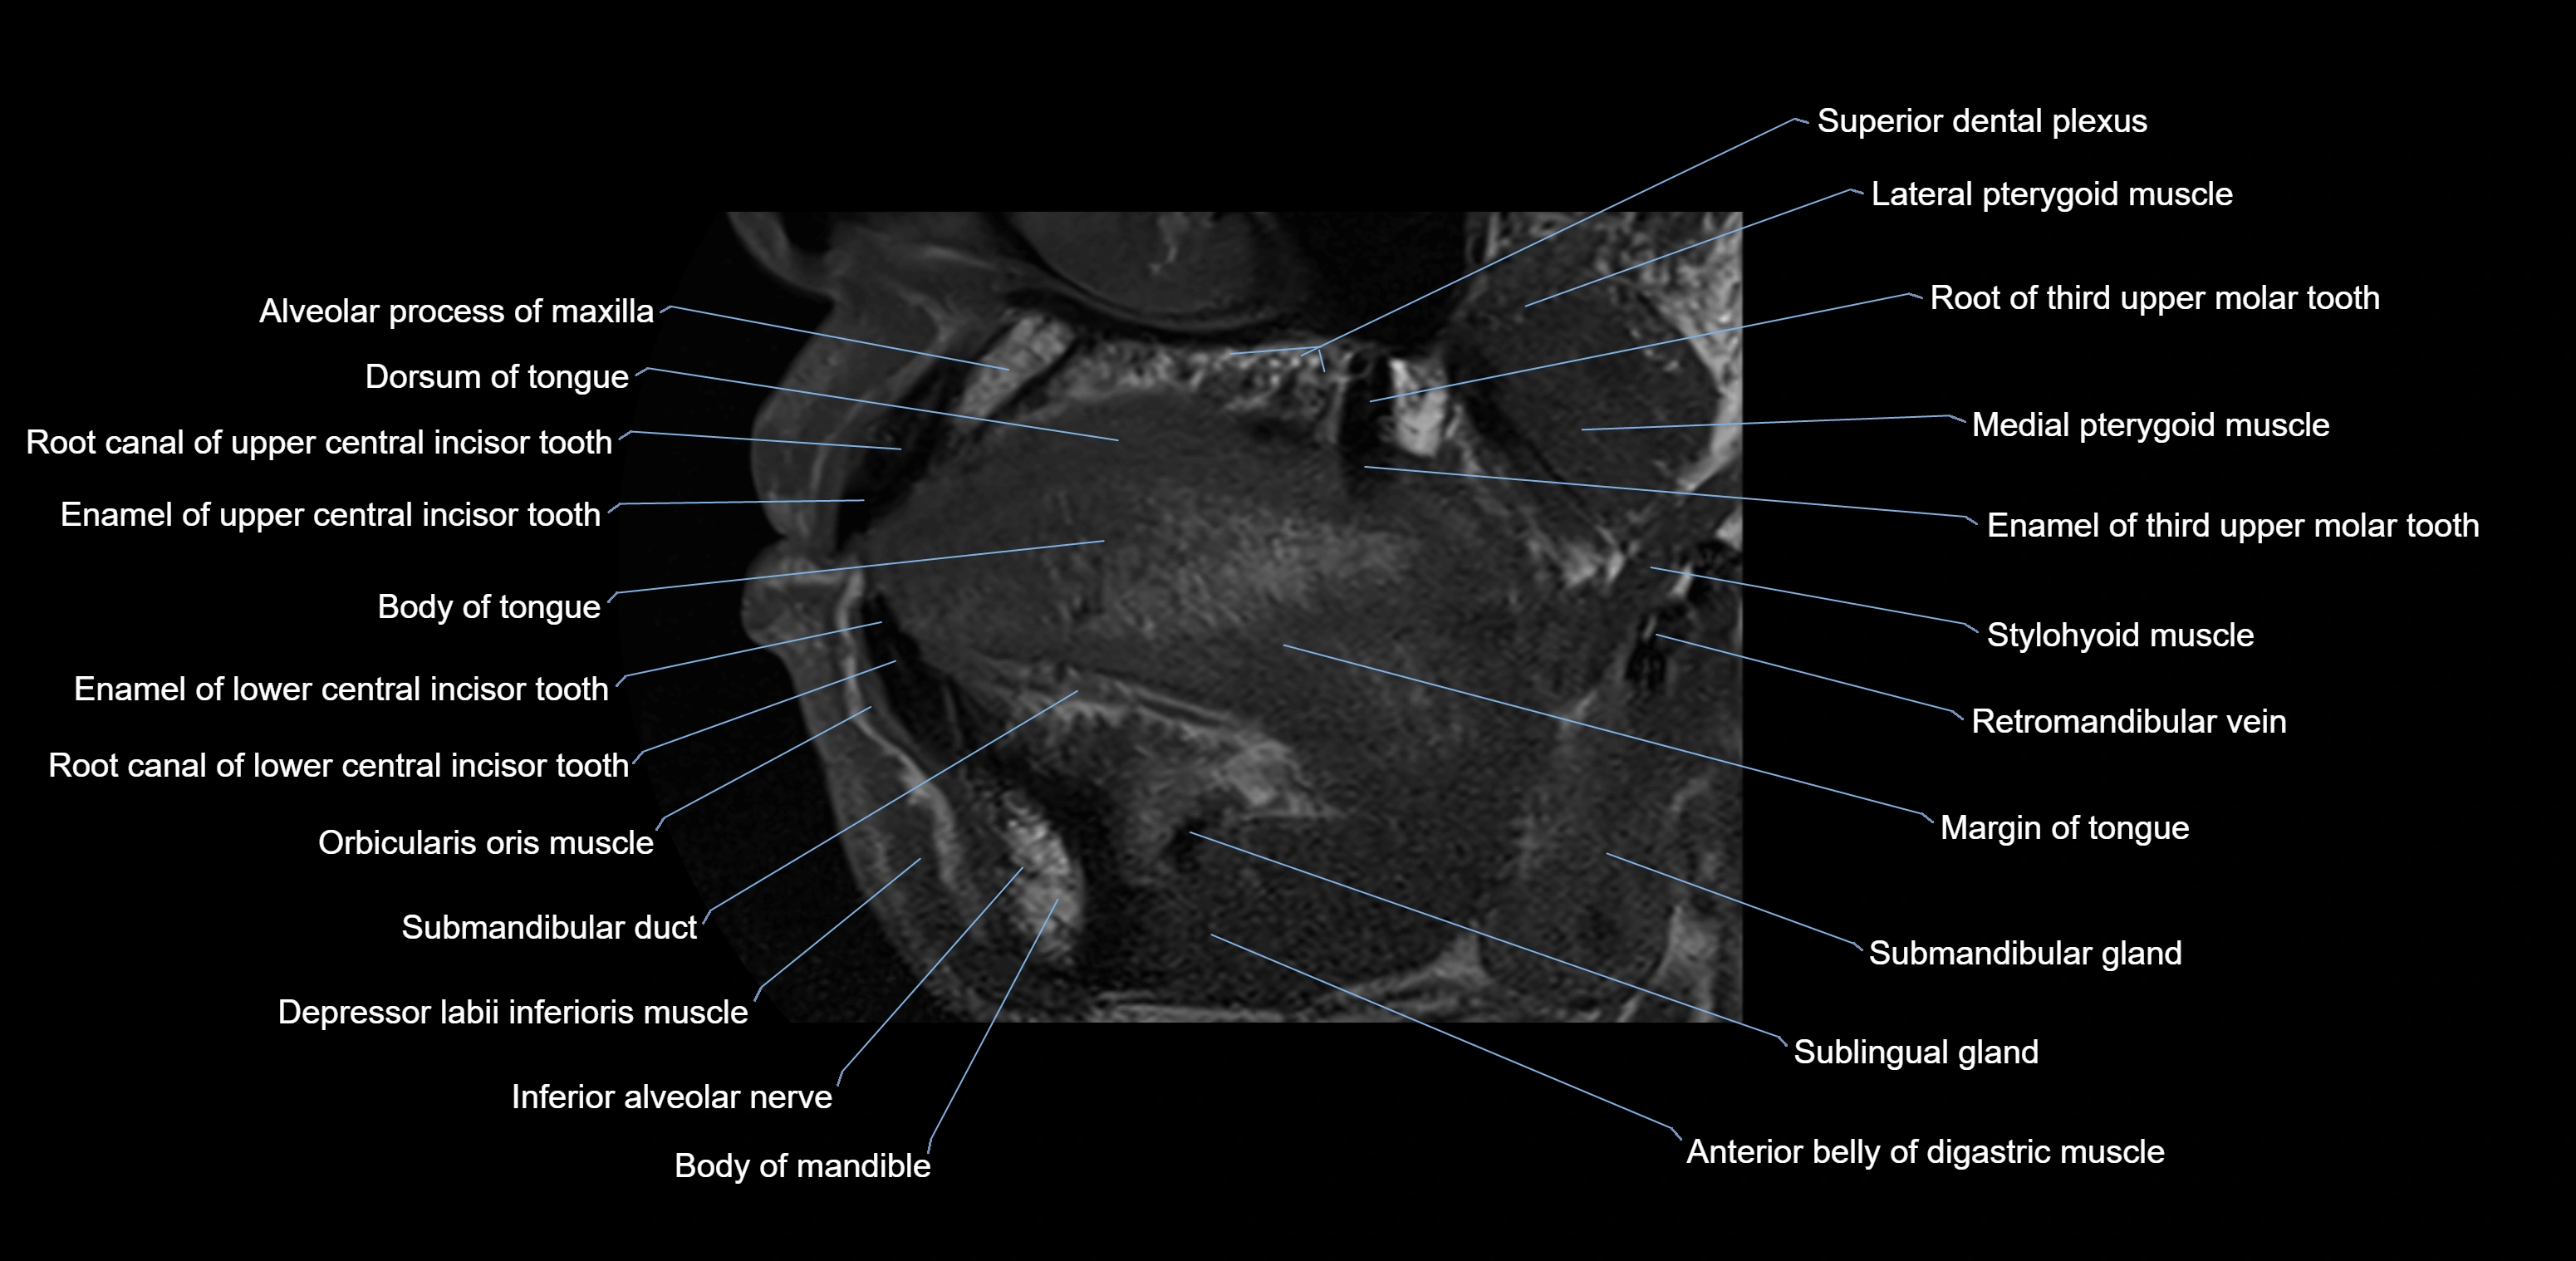

- Body of tongue

- Dorsum of tongue

- Inferior alveolar nerve

- Orbicularis oris muscle

- Body of mandible

- Anterior belly of digastric muscle

- Stylohyoid muscle

- Superior dental plexus

- Root canal of lower canines tooth